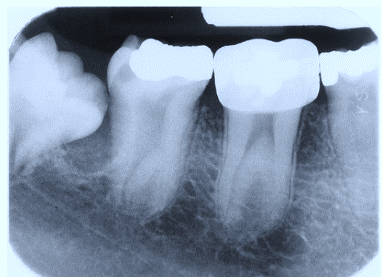

2. (Select ONE OR MORE correct answers)

The radiograph shows evidence of